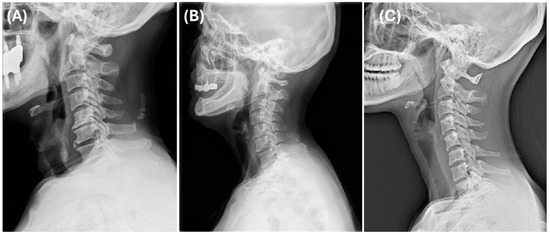

Background and Objectives: The foramen lacerum (FL), located at the base of the skull, is generally considered the safest anatomical pathway for accessing the internal carotid artery (ICA) and the vidian canal (VC) during surgical procedures. We aime...